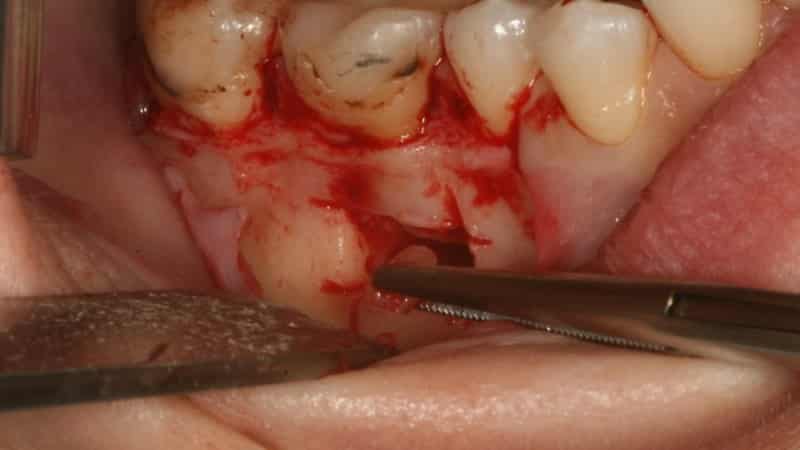

- Подготовка области. Врач обеспечивает удобный доступ к верхушке зуба. Сначала выполняется надрез десны, после чего лоскут ткани отгибается, открывая доступ к челюстной кости. Затем стоматолог находит участок кости корня, где было выявлено образование. В этом месте хирург делает небольшое отверстие с помощью стоматологических боров и бормашины.

- Резекция зуба. Врач использует отверстие для нахождения верхушки корня и расположенной рядом кисты. С помощью бормашины хирург производит резекцию (удаление) верхушки корня. Затем с помощью пинцета удаляется обломок верхушки и связанное с ней патологическое образование из образовавшейся раны.

- Наложение швов. Завершающим этапом является санация ротовой полости и промывание раны антибактериальным раствором. После этого врач сшивает слизистую десны, устанавливая между швами дренаж для оттока крови и сукровицы. Затем на полчаса к области операции прикладываются холодные предметы, и накладывается давящая повязка. Это помогает уменьшить послеоперационный отек и гематому в зоне резекции. Кушать можно не ранее чем через 3-4 часа после процедуры. Дренаж удаляется через несколько дней.